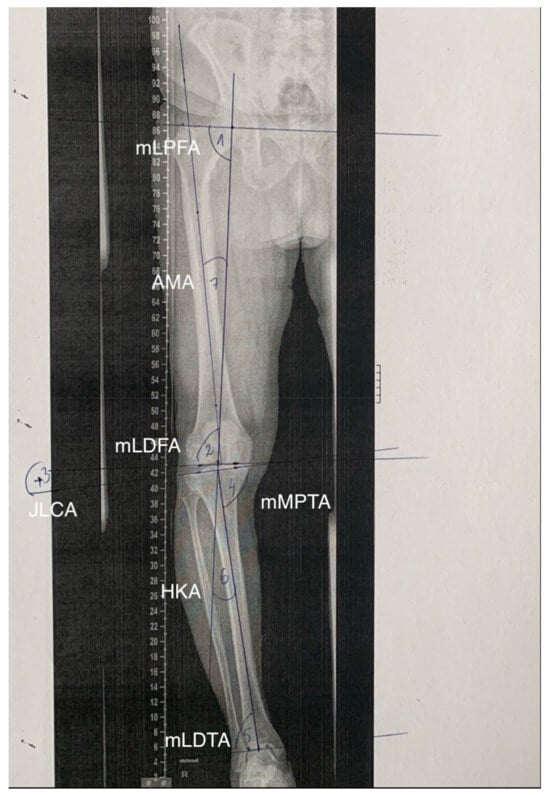

2.1. Manual Measurements